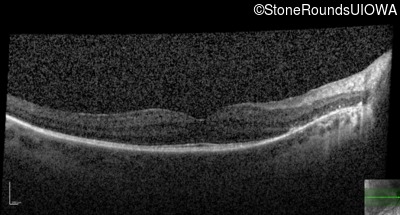

OCT Stack

20/32

20/32 -1

20/30 -2

20/32 -2

20/40

20/25 sc